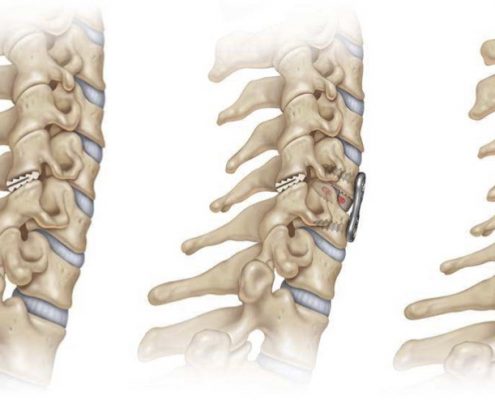

El sistema DTRAX® se compone de 2 cuñas de titanio que se introducen entre las facetas articulares cervicales para conseguir un aumento del espacio foraminal produciendo así la descompresión de la raíz o raíces nerviosas comprimidas a través de la distracción facetaria a la vez que produce una fijación estable de la articulación en el nivel implantado favoreciendo la fusión. Todo ello se realiza mediante un abordaje mínimamente invasivo gracias a un instrumental especialmente diseñado para ello.

DTRAX® está indicado para su uso en pacientes esqueléticamente maduros con patología degenerativa discal de la columna cervical (C3 a C7) con acompañamiento de radiculopatía y/o dolor facetario. La distracción facetaria que produce el DTRAX® hace que el espacio foraminal aumente aproximadamente en un 20% además de producir una estabilización de la articulación mayor en movimientos de rotación axial y movimientos laterales e igual en flexo- extensión si lo comparamos con la estabilización que produce una caja y una placa colocada mediante un abordaje anterior tradicional.